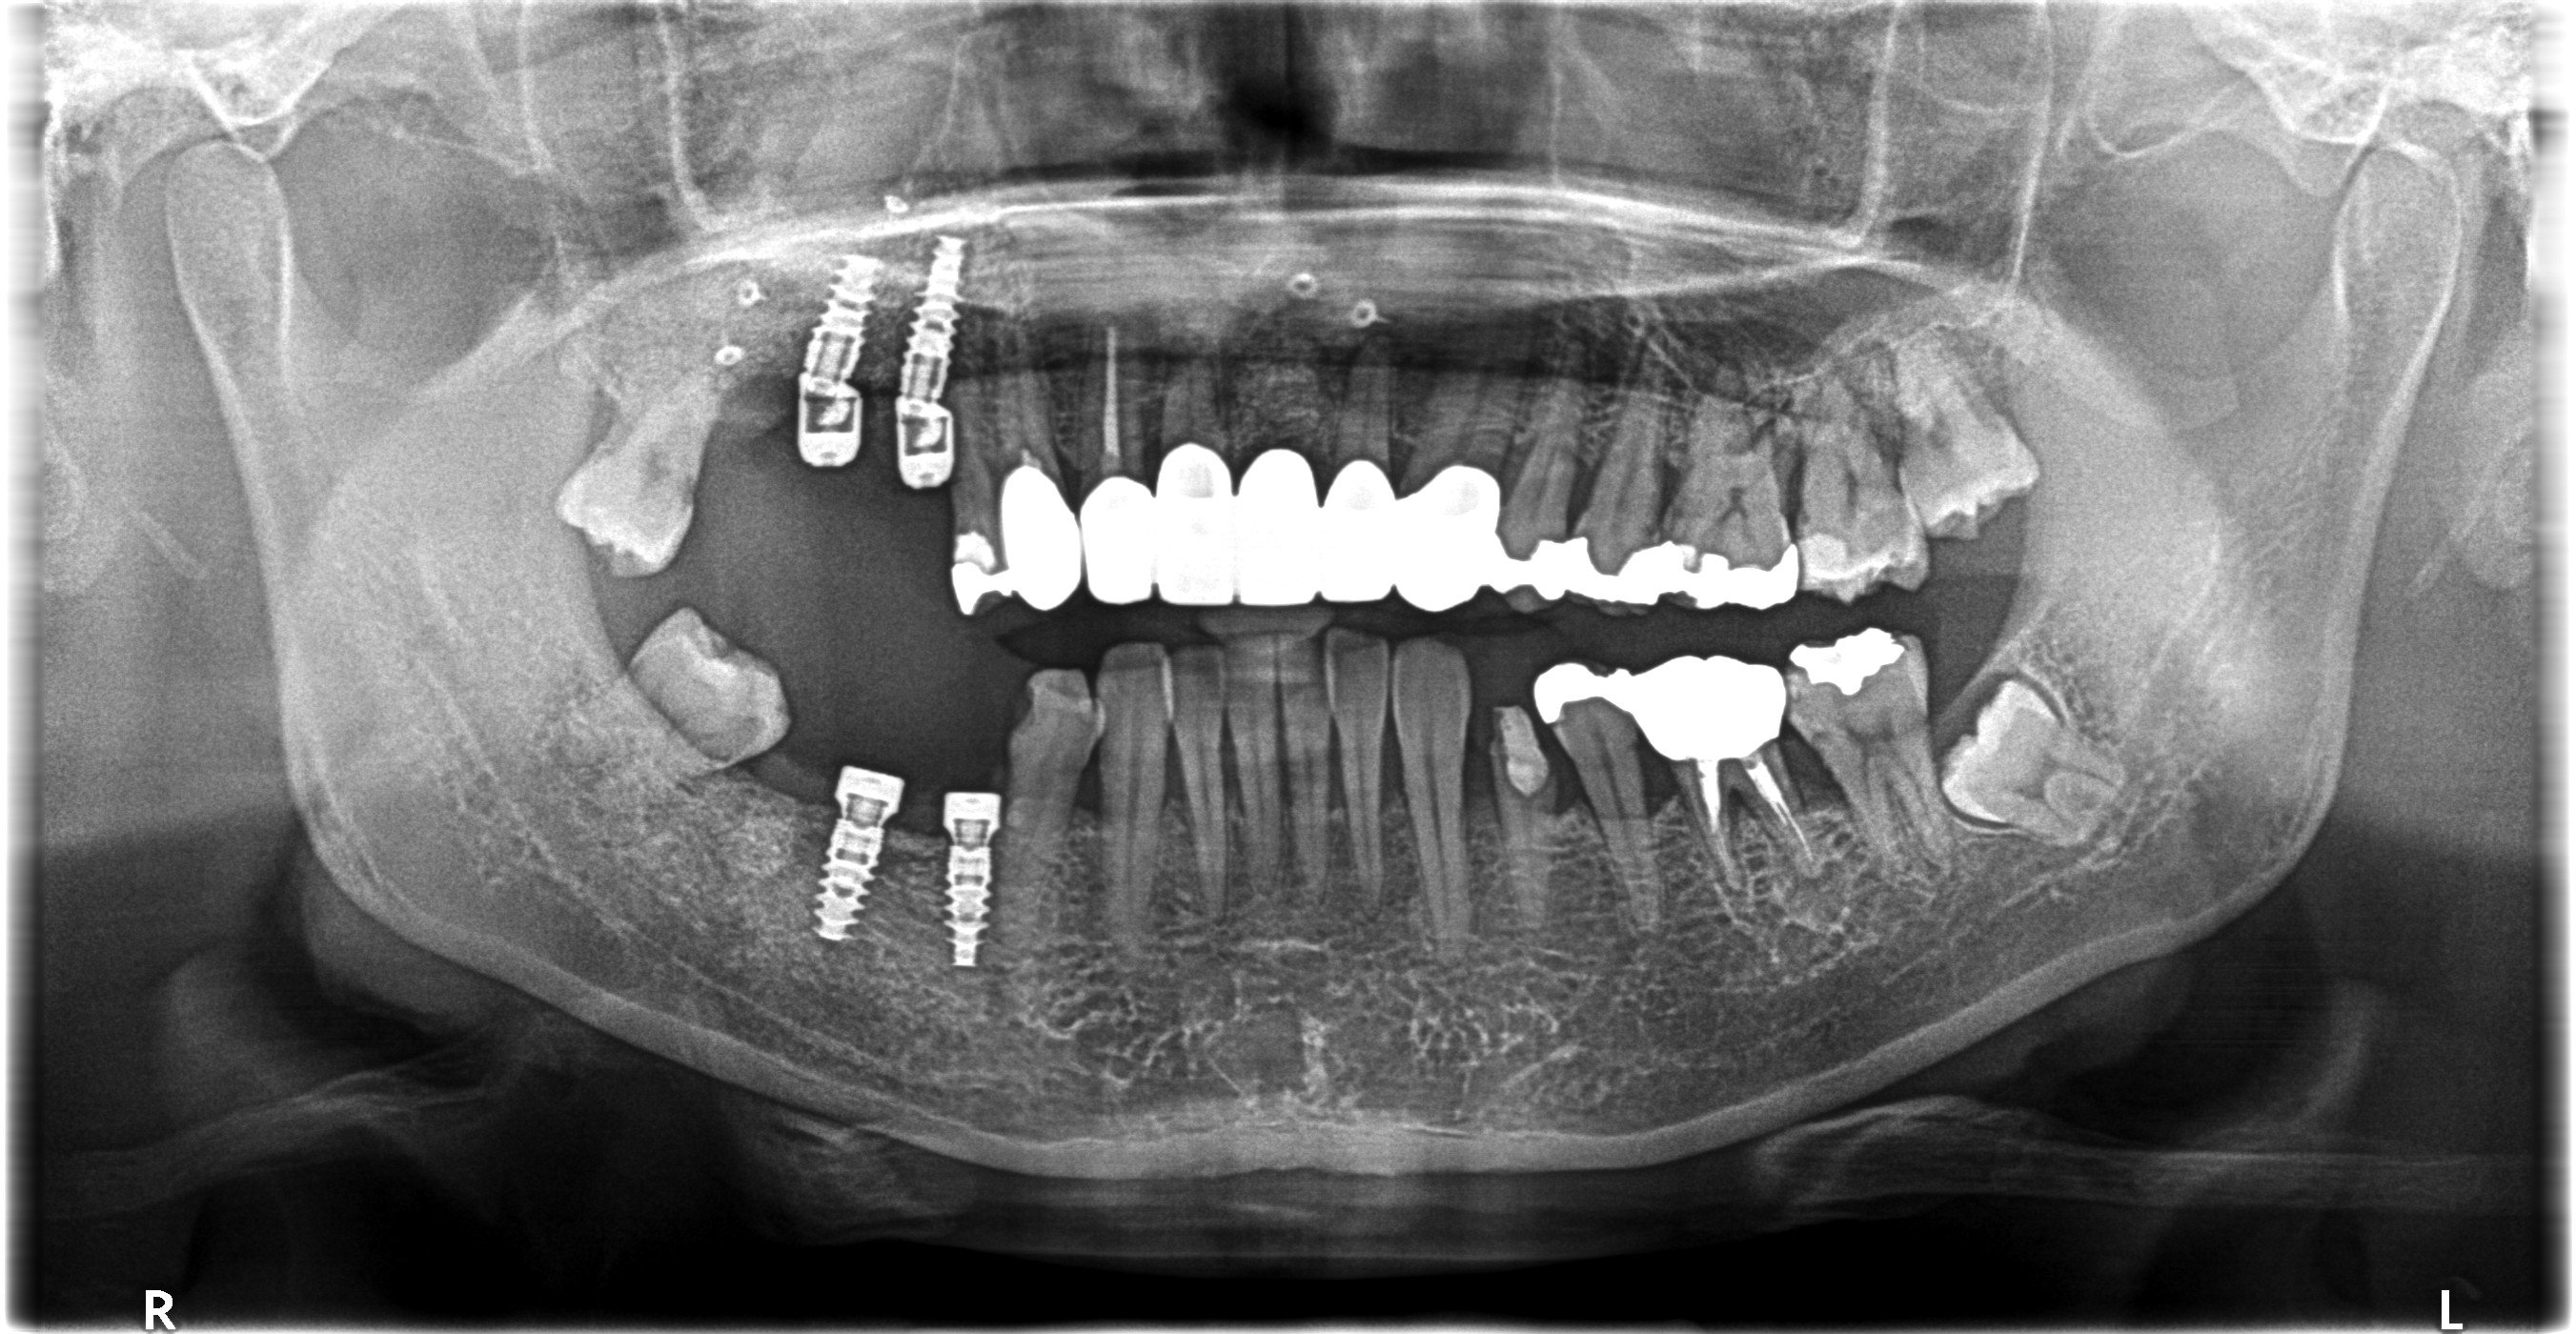

今回は右上下にImplant治療を行なったケースのご紹介です💡

こちらが初診時のレントゲンになります

根尖性歯周炎と歯周病が重なり保存が難しかったため抜歯をして右上はサイナスリフト、右下はGBRを行いました

そして骨硬化確認後Implant治療になりました

🦷治療内容:GBRとサイナスリフト➡︎Implant